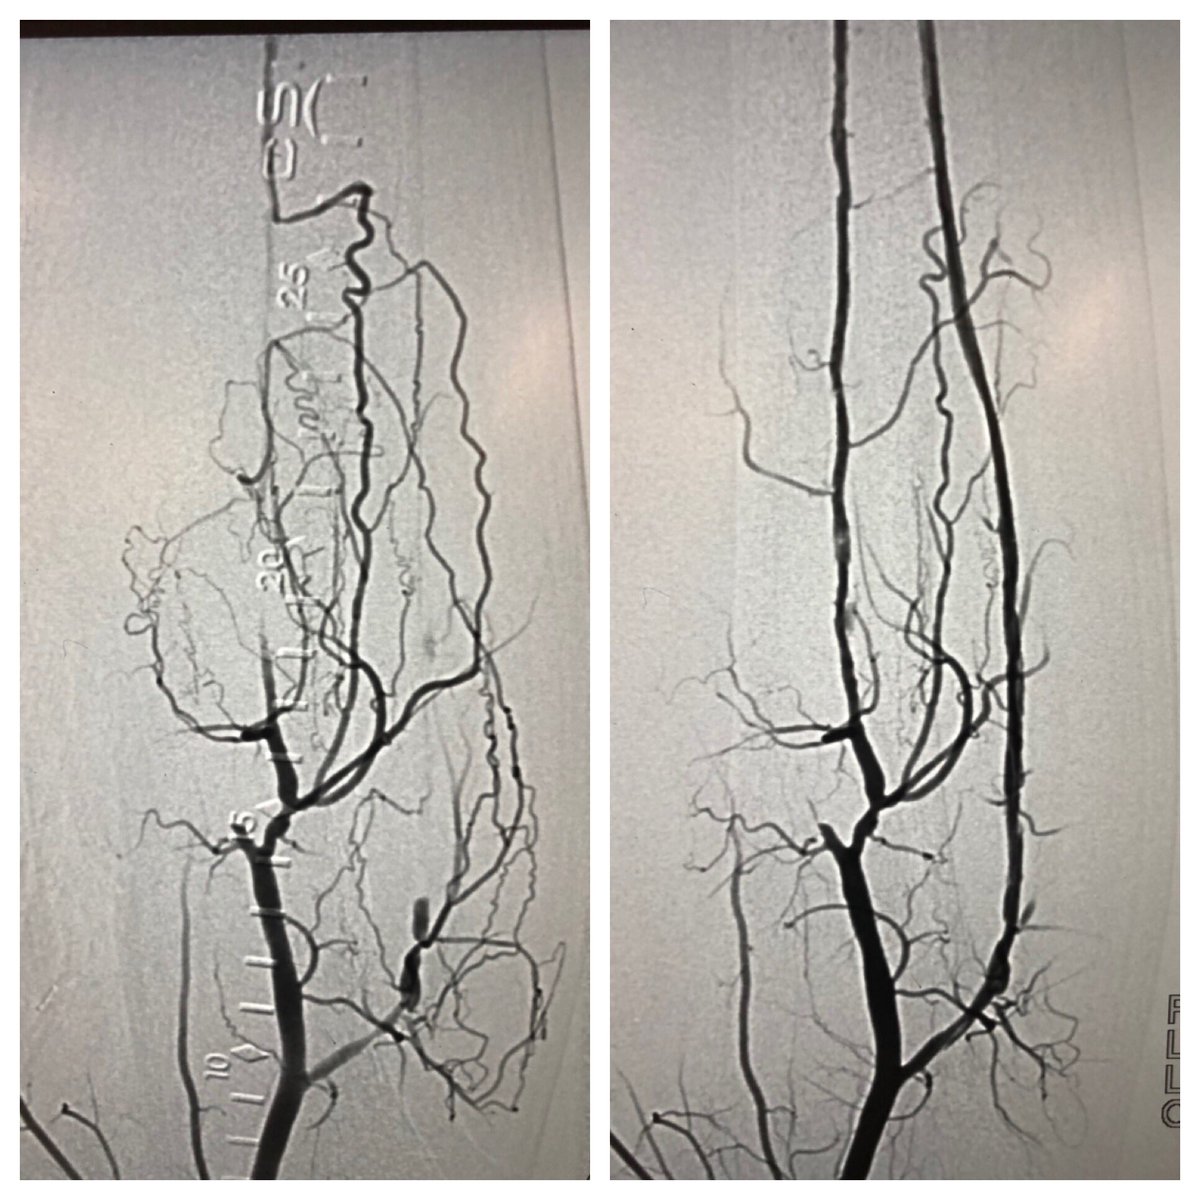

Collaborative approach to treat #CLI patient. VS referral to treat distal AT and TPT after fem-pop bypass. TAMI/dual pedal access for retrograde crossing of previous crushed TPT stent, to protect graft flow into AT & treat distal AT. Merit Ideal (slender) sheaths 3Fr OD #SCAIPAD